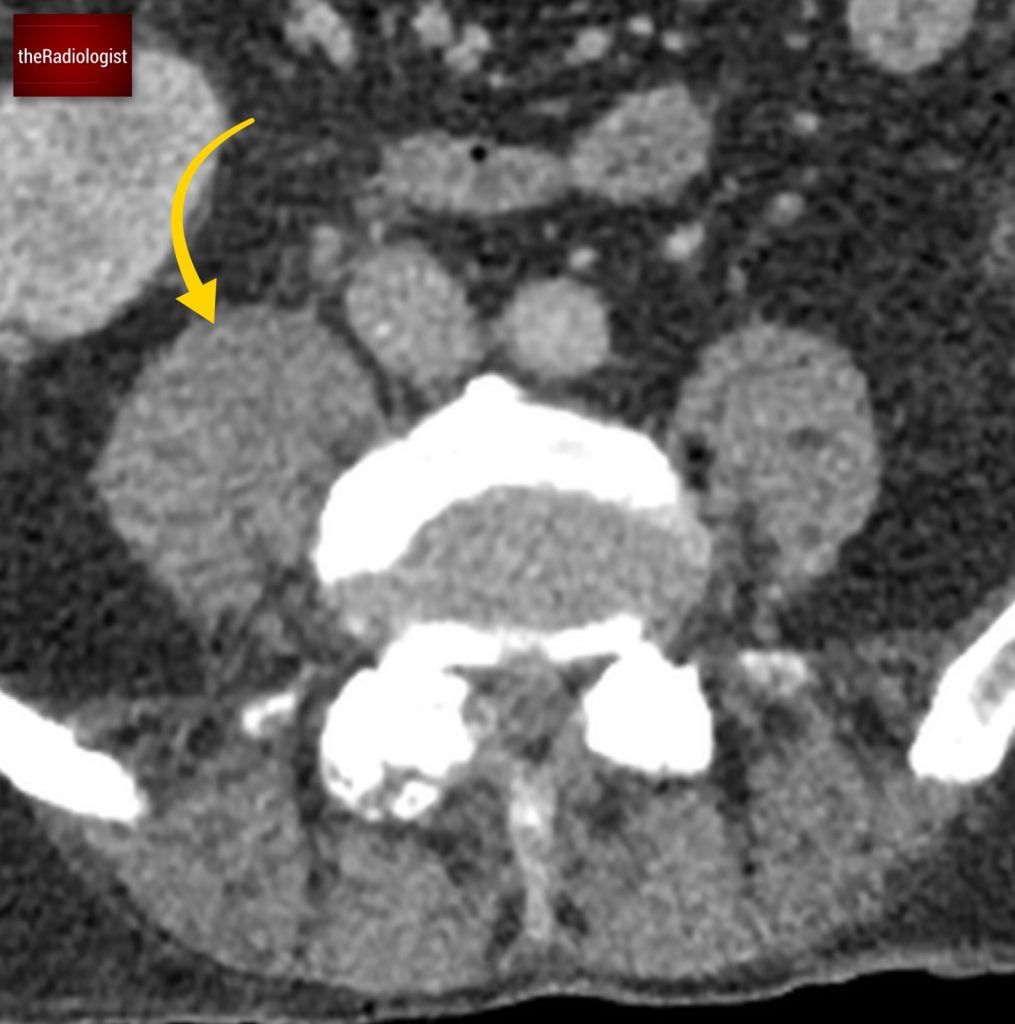

If we look at the psoas muscles on this scan below we can see there is some asymmetry . The right psoas is larger than the left and we’ve lost some of the fat planes within the muscle.

Compare the psoas muscles side by side. The right sided psoas muscle appears expanded with a loss of its normal fat planes.